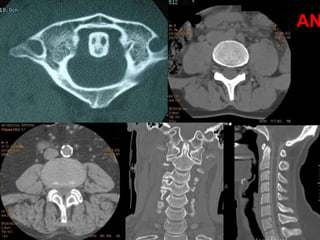

Computerized Tomographic

Imaging

CT

PHYSICAL PRINCIPLES OF COMPUTED TOMOGRAPHY

AN

CT Myelograms